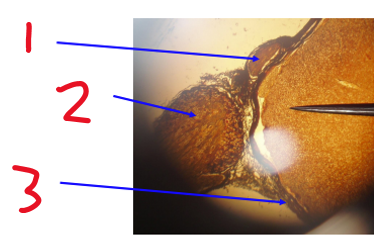

Name structure 1

Dorsal root

Name structure 2

Dorsal root ganglion

Name structure 3

Ventral root